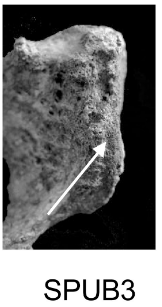

Demi-face antérieure (SPUB)

Changements morphologiques de la demi-face antérieure liés à la formation du rempart ventral.